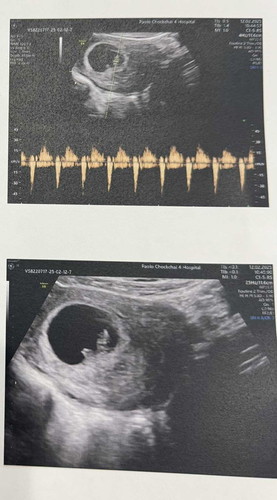

6W+5D. แข็งแรงหัวใจเต้นดีมาก

ใครทีม6Weekบ้างคะ ขอให้แม่ๆและเบบี๋แข็งแรงๆนร้า ทางนี้แพ้ท้องหนักมากตั้งแต่5Week